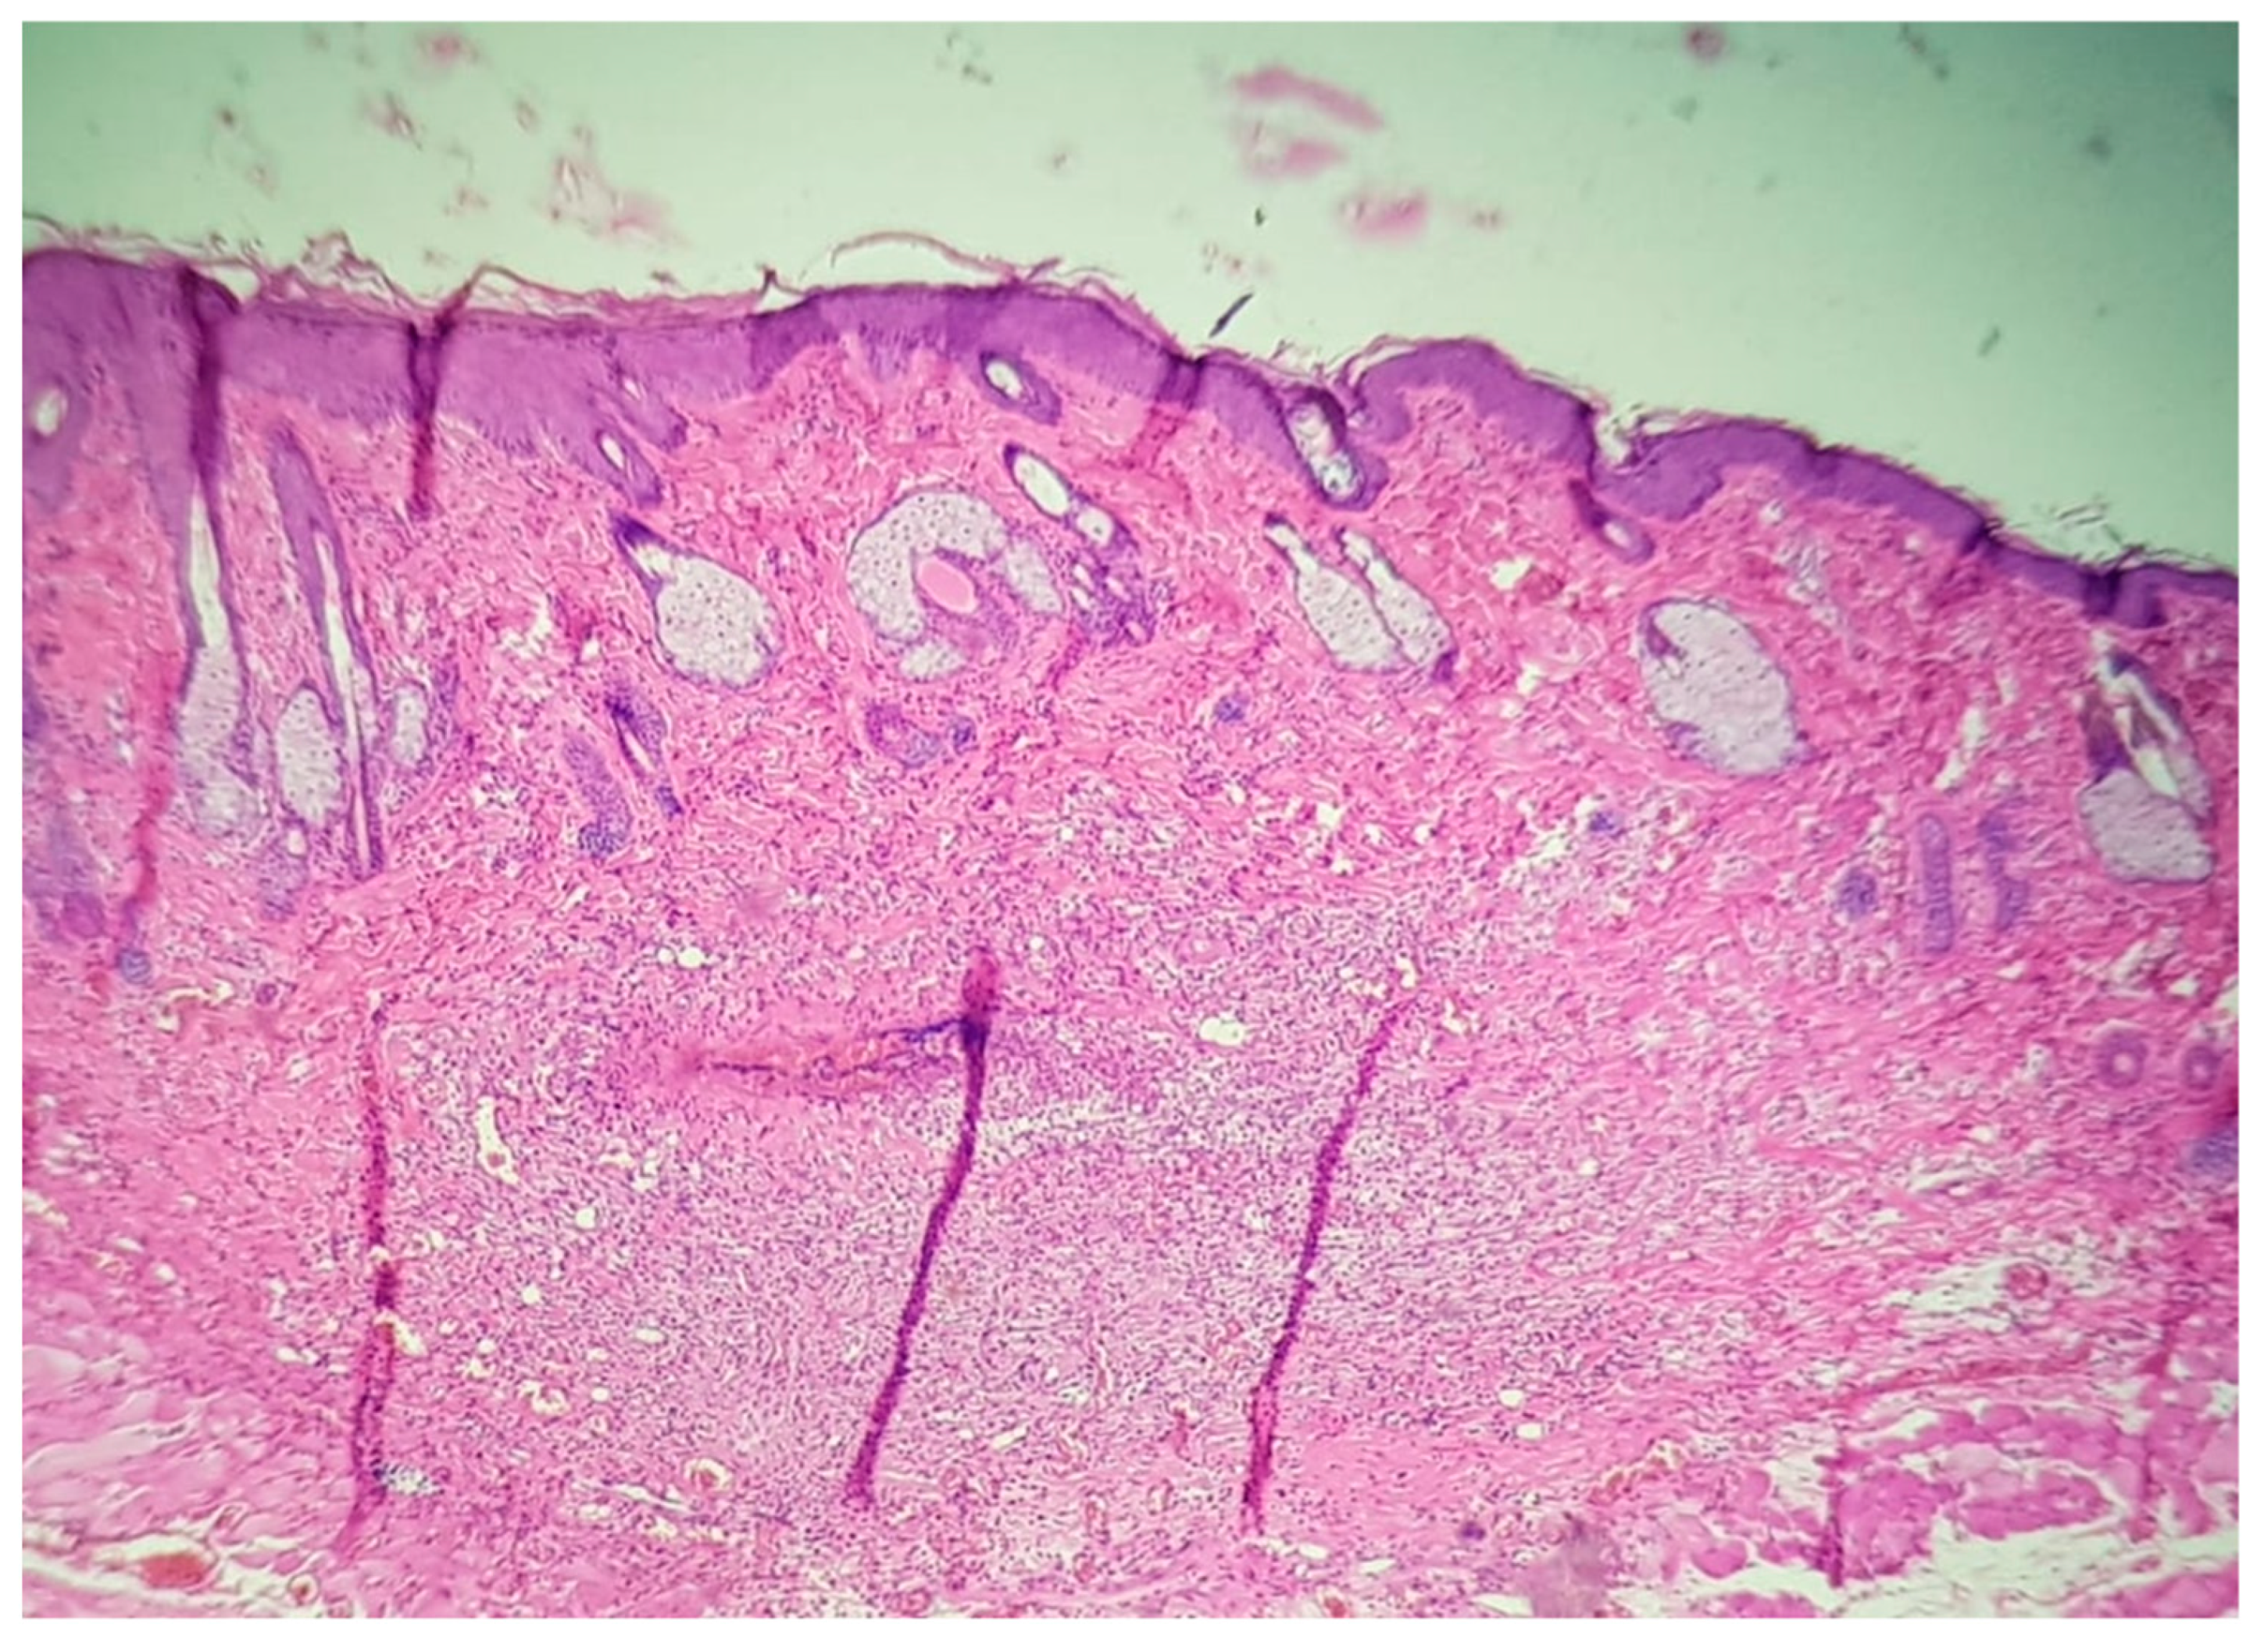

2.3. Histological Evaluation

| Batch Number | Rat Number | Evaluation of the Inflammatory Infiltrate | |

|---|---|---|---|

| Injection of 0.65 mg/mL MB | Injection of 1 mg/mL PRO | ||

| Batch 1 | 1 | Medium | Medium |

| 2 | Medium | Rich | |

| 3 | Medium | Medium | |

| 4 | Medium | Rich | |

| 5 | Absent | Absent | |

| 6 | Absent | Absent | |

| Batch 2 | 1 | Medium | Medium |